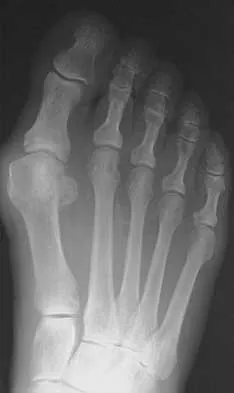

An 83-year-old woman with diabetes mellitus has a history of recurrent infection over the medial aspect of her great toe and has had a painless bunion for the past 45 years. Shoe wear modifications have failed to provide relief. Pedal pulses are palpable. Figures 30a and 30b show the clinical photograph and radiograph. Management should now consist of

Explanation

The presence of recurrent breakdown over the medial eminence despite shoe wear modifications is an indication for surgery. A number of factors must be considered when deciding on an appropriate course of treatment. These include age, activity level, joint congruency, joint degeneration, and the patient's symptoms and expectations. The indications for a simple bunionectomy are rather limited. In this patient, the goal of surgery is to alleviate the recurrent infection by removal of a large medial eminence. Because the bunion is painless and long-standing, it does not warrant treatment. Mizel MS, Miller RA, Scioli MW (eds): Orthopaedic Knowledge Update: Foot and Ankle 2. Rosemont, IL, American Academy of Orthopaedic Surgeons, 1998, pp 123-134.